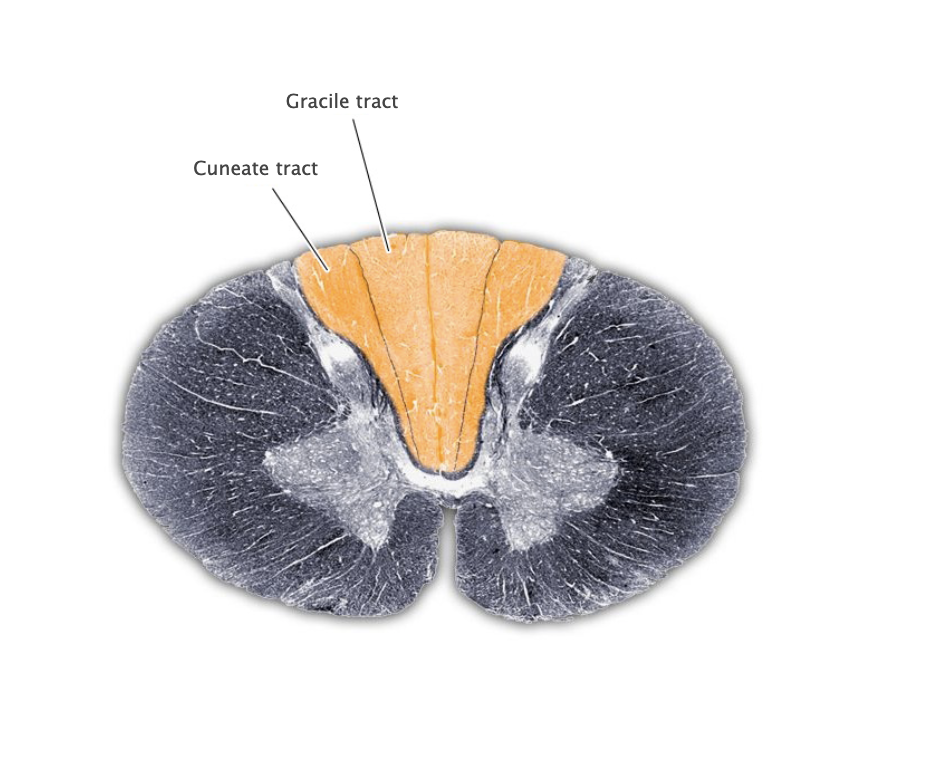

Dorsal columns

White matter region between the dorsal horns of the spinal cord containing the gracile and cuneate tracts.

Gracile tract

Medial portion of the dorsal columns comprising the central processes of dorsal root ganglion axons that convey mechanosensory information from the lower body. Also referred to as the "fasciculus gracilis."